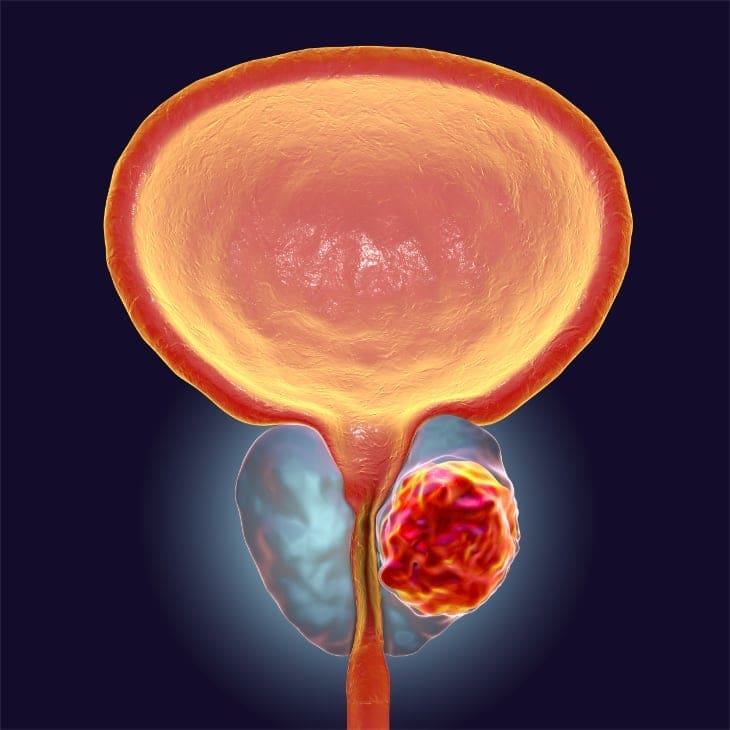

Located deep inside the groin between the base of the penis and the rectum, the golf-ball-sized prostate gland, along with the seminal vesicles behind the prostate, produces seminal fluid which mixes with sperm from the testes to help sperm travel. Prostate cancer occurs when healthy cells in the prostate begin to mutate and grow out of control. When the abnormal cells clump together, they form a cancerous tumor. Researchers still don’t have all the answers about what triggers changes to prostate cells, but know that genetics, family history, ethnicity, a high-fat diet and obesity are all risk factors.

Staging refers to how much the cancer has grown and spread. Is it confined locally within the prostate? Has it spread beyond the prostate and into the lymph nodes, or metastasized to the bones? In cases where the Gleason score is on the high side, additional tests such as an MRI, CT scan or bone scan will be conducted to help stage the prostate cancer more precisely. Based on these reports, the American Joint Committee on Cancer TNM (Tumor, Node, Metastasis) Staging System is used to describe how far the cancer has spread. The TNM system is based on three important pieces of information:T1a – cancer found in 5% of TURP specimens